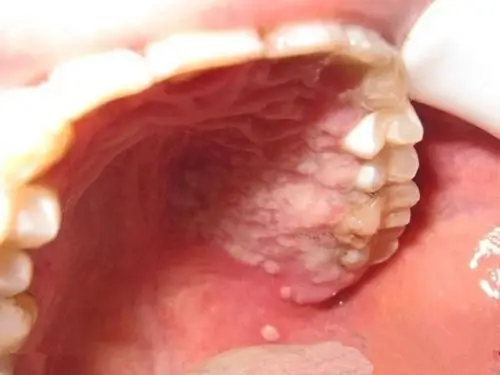

术后立即复查头部ct,右侧基底节区高密度影,考虑造影剂强化!